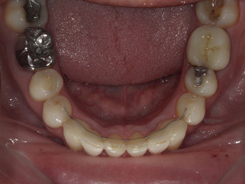

Arcade mandibulaire avant traitement orthodontique, séquelles de maladie parodontale

Après traitement orthodontique et réalisation d’une attelle fibrée (courtoisie Dr Patrick Fournier)